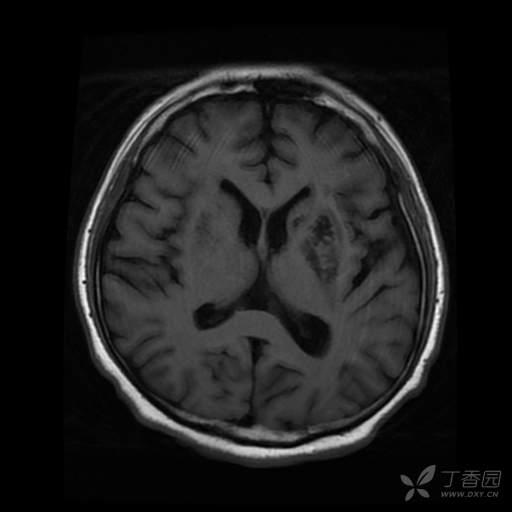

病人入院时意识清,对答如流,入院第 2 天心跳骤停抢救成功后出现言语减少。入院 33 天完善颅脑 MRI ,提示双侧基底节区及放射冠区异常信号;脑白质变性,脑内多发脱髓鞘灶;双侧小脑半球萎缩;右侧上颌窦囊肿。

导致患者意识状态改变的原因是什么?从这份头颅 MRI 能得出什么诊断?